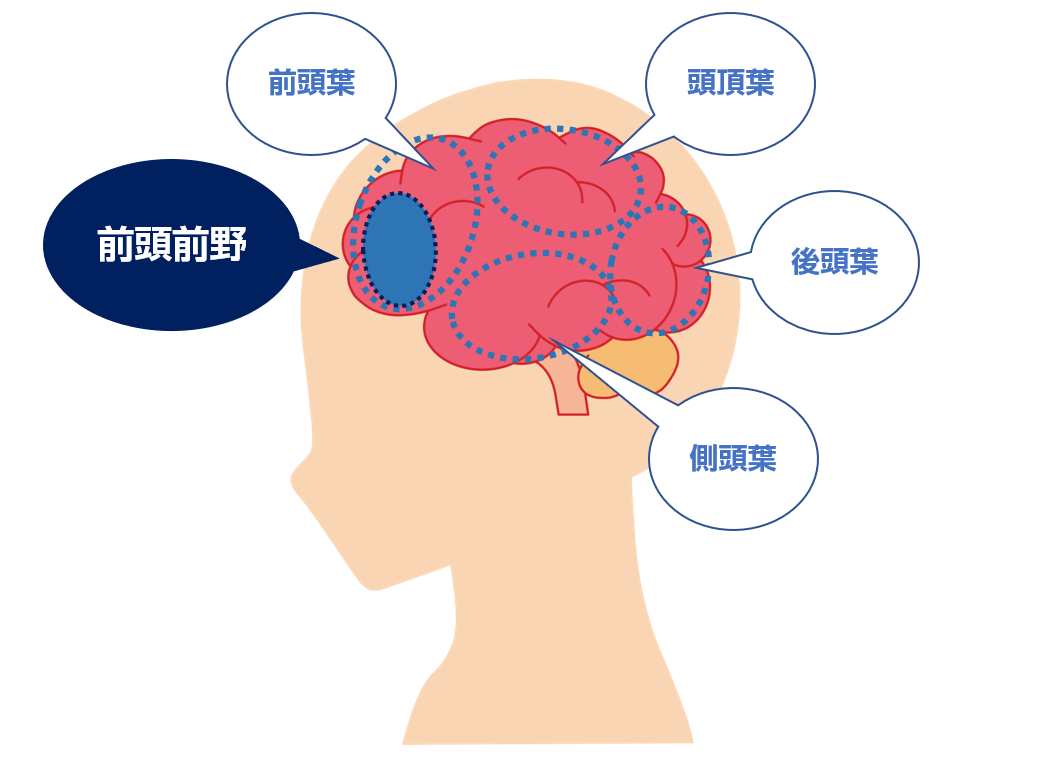

脳の構造 大脳を4つの領域に分けるランドマーク

Images Of 前頭前野 Japaneseclass Jp

脳の構造 大脳を右脳と左脳に分ける脳の溝

脳の構造と役割 子供の脳の発達のための 脳育jp 子どもに健やかな成長と健全な発達を